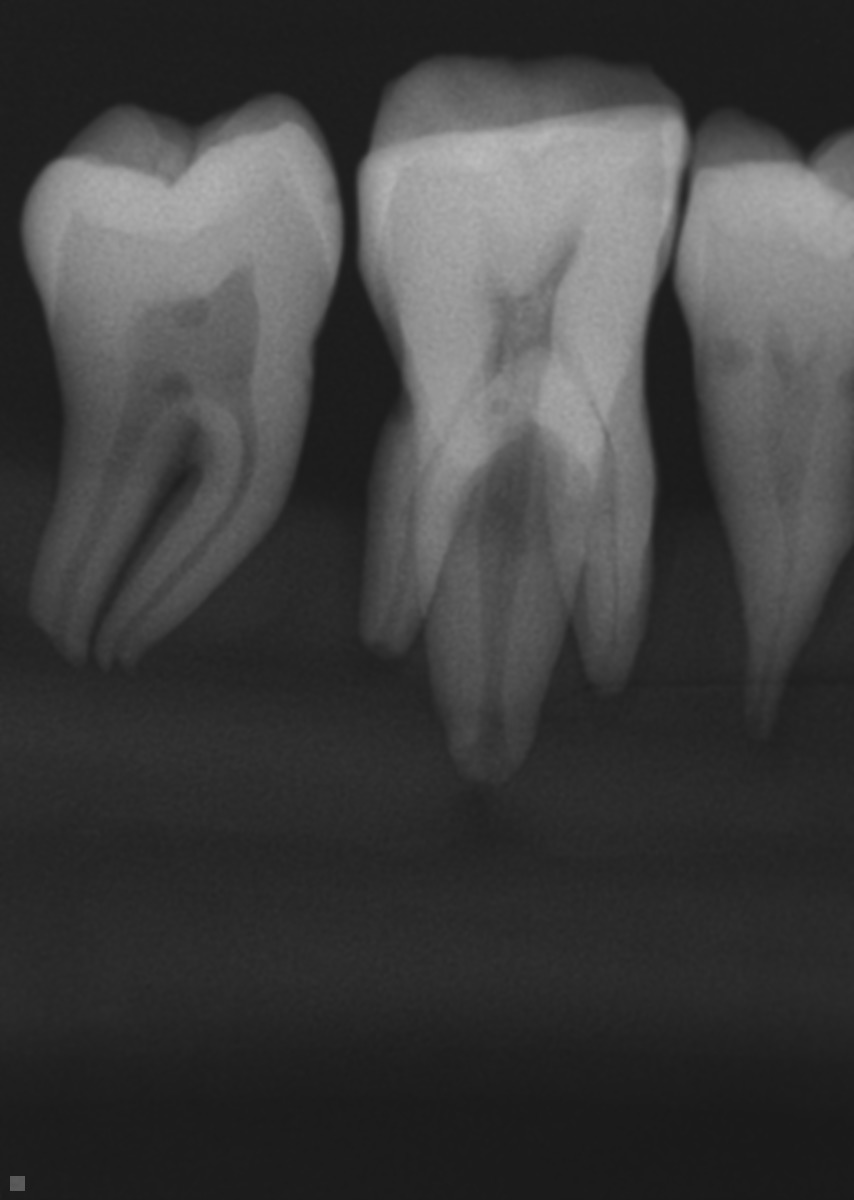

CBCT With Different Voxel Sizes Versus Digital Periapical Radiography in Detection of External Resorption

Objectives: To compare the efficacy of cone beam computed tomography (CBCT) images acquired with 2 different voxel sizes, and digital periapical radiographs in diagnosing external resorption lesions.

Methods: This study included 280 root surfaces from a sample of 46 extracted permanent teeth. Surfaces were randomly divided into two groups; Group A: Experimental group (N=138) and Group B: control (N = 142). Group A was further divided to 9 subgroups according to the size of the lesion created: A1 , A2, and A3, and according to the location of the lesion; apical (A), middle (M) or cervical (C) thirds. Group A cavitated lesions were simulated by drilling holes on the root surfaces with a size ¼, 2 and 4 round bur for subgroups A1, A2 and A3 respectively. The teeth were mounted in sticky wax and a rubber glove filled with water was used to simulate soft tissues. All teeth were radiographed under standardized conditions; Direct digital images were obtained using a Schick Elite direct digital intraoral CCD sensor to obtain periapical radiographs. I-CAT 17-19 model scanner was used to obtain the CBCT scans with a field of view 8 X 5 cm, the scans were obtained with 2 voxel sizes; 0.125 and 0.3.

Results: CBCT with 0.125 voxel size showed statistically significantly higher number of correctly diagnosed lesions than both CBCT with 0.3 voxel size and Periapical radiographs. Periapical radiography was significantly less accurate than CBCT scans with both voxel sizes. Comparison between the different groups shows a higher percentage of correctly diagnosed A3 lesions (94.79%) compared to 87.04% A2 lesions, and 64.07 % A1 lesions. The percentage of missed lesions on Buccal/lingual surfaces was 14.29% compared to only 3.29 % on proximal surfaces. The Chi Square test suggests no difference between observers (p-value=0.93)

Conclusions: CBCT scans are more accurate in diagnosing external root resorption compared to Periapical radiographs. A smaller voxel size is preferred and yields a more accurate diagnosis . Buccal and lingual root resorption is more challenging to diagnose compared to proximal resorption lesions.